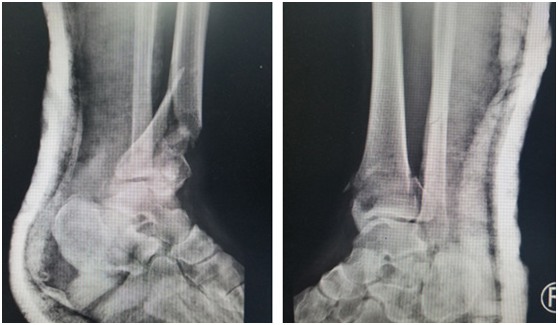

(術(shù)前)

在仁慈醫(yī)院,急診醫(yī)生給華大姐完善各項(xiàng)檢查,發(fā)現(xiàn)她的傷情很?chē)?yán)重:雙pilon骨折,雙跟骨骨折,腰椎多發(fā)骨折。急診醫(yī)生立刻聯(lián)系足踝科徐明亮主任前來(lái)會(huì)診,徐主任仔細(xì)檢查了華大姐的病情,安排她先進(jìn)行距骨牽引,消腫一周,等待合適的手術(shù)時(shí)機(jī)。

“病人雙側(cè)跟骨粉碎性骨折,脛骨遠(yuǎn)端粉碎性骨折,受傷暴力大,周?chē)浗M織損傷也比較重,短時(shí)間內(nèi)局部出現(xiàn)張力性水泡,早期切開(kāi)后,一是容易導(dǎo)致傷口難以縫合,另外也增加了感染的機(jī)會(huì),所以要在消腫以后,再給她切開(kāi)復(fù)位內(nèi)固定,減少患者傷口感染的幾率。”徐明亮主任說(shuō)。